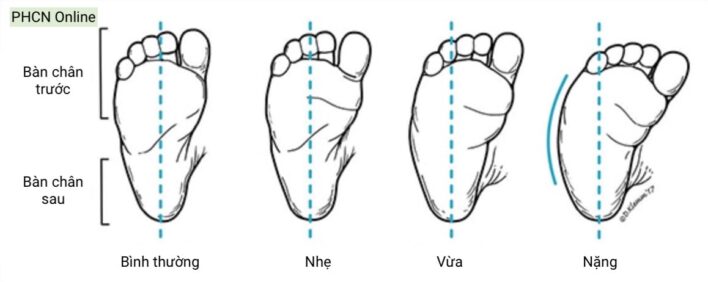

Đánh giá biến dạng xoay ở đoạn bàn chân sử dụng đường chia đôi (lòng) bàn chân (bisector line) sau từ gót chân. Đường này thường đi qua khoảng kẽ ngón II-III, và lệch vào trong hoặc ra ngoài chứng tỏ bàn chân trước bị khép hoặc dạng.

Biến dạng bàn chân khép (lệch vào trong của các xương bàn đốt ở khớp cổ bàn chân), là một chẩn đoán lâm sàng ở trẻ tuổi bú mẹ. Bờ ngoài bàn chân cong lồi thay vì thẳng (hình chữ C), và có thể có nếp gấp mép trong bàn chân. Cần phân biệt biến dạng này với bàn chân khoèo (clubfoot) hoặc bàn chân có biến dạng thêm ở bàn chân sau (skewfoot).

Hầu hết các trường hợp bàn chân khép mềm (flexible) tự điều chỉnh. Có thể hướng dẫn bố mẹ tập kéo dãn bàn chân hàng ngày với trẻ dưới 8 tháng. Trẻ nhũ nhi có bàn chân khép cứng (rigid) có thể cần bó bột nối tiếp (serial casting) trước tuổi biết đi. Trong một số ít trường hợp nặng, có thể cần can thiệp phẫu thuật để có được bàn chân cân bằng, dễ mang giày dép (tuy nhiên cần lưu ý biến chứng sau phẫu thuật rất thường gặp).

Trường hợp trẻ bị bàn chân khép nhẹ kèm theo khép quá mức của ngón cái có thể chỉ định giải phóng gân cơ khép ngón cái vào lúc trẻ được 6-18 tháng tuổi.